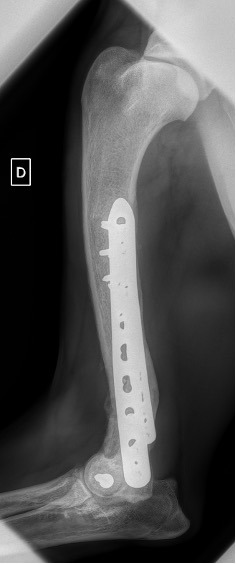

Exemple 1 :

Figure 2 : Post-Op Immédiat

Notre préférence va vers le placement de deux plaques humérales : une médiale de la plus grande taille possible et l’autre latérale, généralement d’une taille inférieure à la première. Dans l’exemple 1 (chat européen), une plaque de 2 mm est utilisée médialement et une plaque de 1,5 mm latéralement. Dans l’exemple 2 (chien Malinois), une plaque de 3,5 mm est utilisée médialement et une plaque de 2,7 mm latéralement.